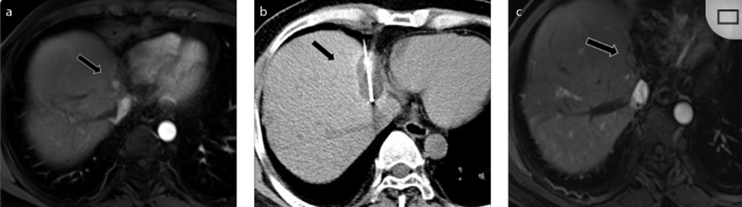

( a ) 轴向 MRI 和 ( b ) 轴向 CT 显示肝S8段有一个16mm的病灶,邻近肝缘。( c )冷冻消融期间CT显示放置了2个冷冻探针,低密度冰球包围病灶。(d)术后1个月随访 CT显示冰球对应的坏死区域,未见复发。(f)与基线影像(g)相比,12个月后的FDG-PET/CT显示未见FDG摄取。

(a)轴向CT显示病变位置毗邻心脏和上腔静脉(黑色箭头)。1个月后的轴向(e)和冠状位(f)增强CT扫描显示低密度区域,由于肉芽组织反应引起的边缘增强。